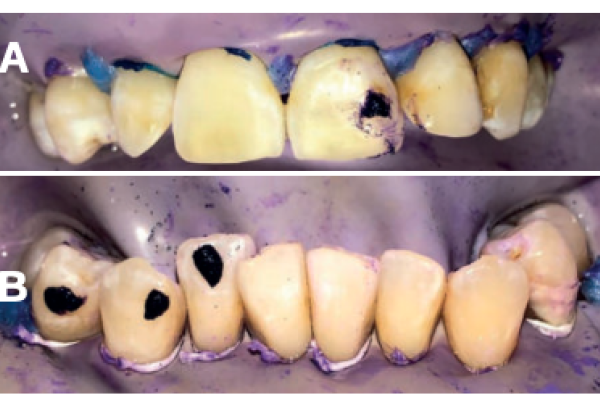

Tratamiento de recesiones gingivales unitarias y múltiples en la zona anterior mandibular mediante técnica de Edlan-Mejchar modificado. Descripción de la técnica quirúrgica y resultados